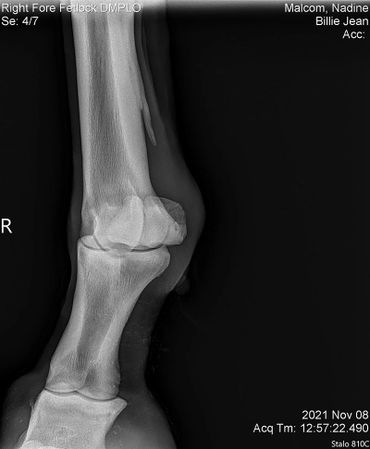

The only issue I'm still working on with her is that she still doesn't like to have a saddle put on her back. Once it's on she's good to go. I've had this mare checked for everything! She got scoped for ulcers, checked for kissing spine, her knees x-rayed since she's a little over the knee and her coffin/ fetlock x-rayed. She's totally fine! I assume that this poor girl was probably ridden in a really poor fitting saddle for years which brought her great uncomfort. I believe over time she will eventually get over this but I can't stress enough that patience is required while saddling her!

BJ also had hr knees, fetlock and coffin joint x-rayed on July 7, 2022. Her vet bill was $185.

We did a full wellness and lameness exam and everything looked pretty good. She showed some soreness in her right front fetlock so we did some x-rays but nothing really to see that would raise concern. We also did x-rays on her stomach and it showed she has some sand which we have been treating with Sand Clear.We didn't do x-rays on her knees. Dr. Johnson said she's probably got some fluid in there because it looks like she used to hit her knees on something a lot so we are rubbing some DMSO on it to relieve some of the swelling.Billie Jean also got a dental float. After examining her teeth closer it turns out she is more like 18-20 years old.